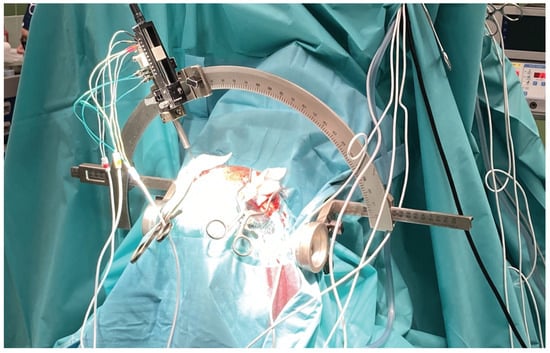

2.3.1. Intraoperative Neuronavigation

- Şahin, E.; TALU, M.F. AI-Guided Optimal Trajectory Selection in Stereotactic Brain Biopsy. Artif. Intell. Stud. 2025, 8, 1–19. [Google Scholar] [CrossRef]